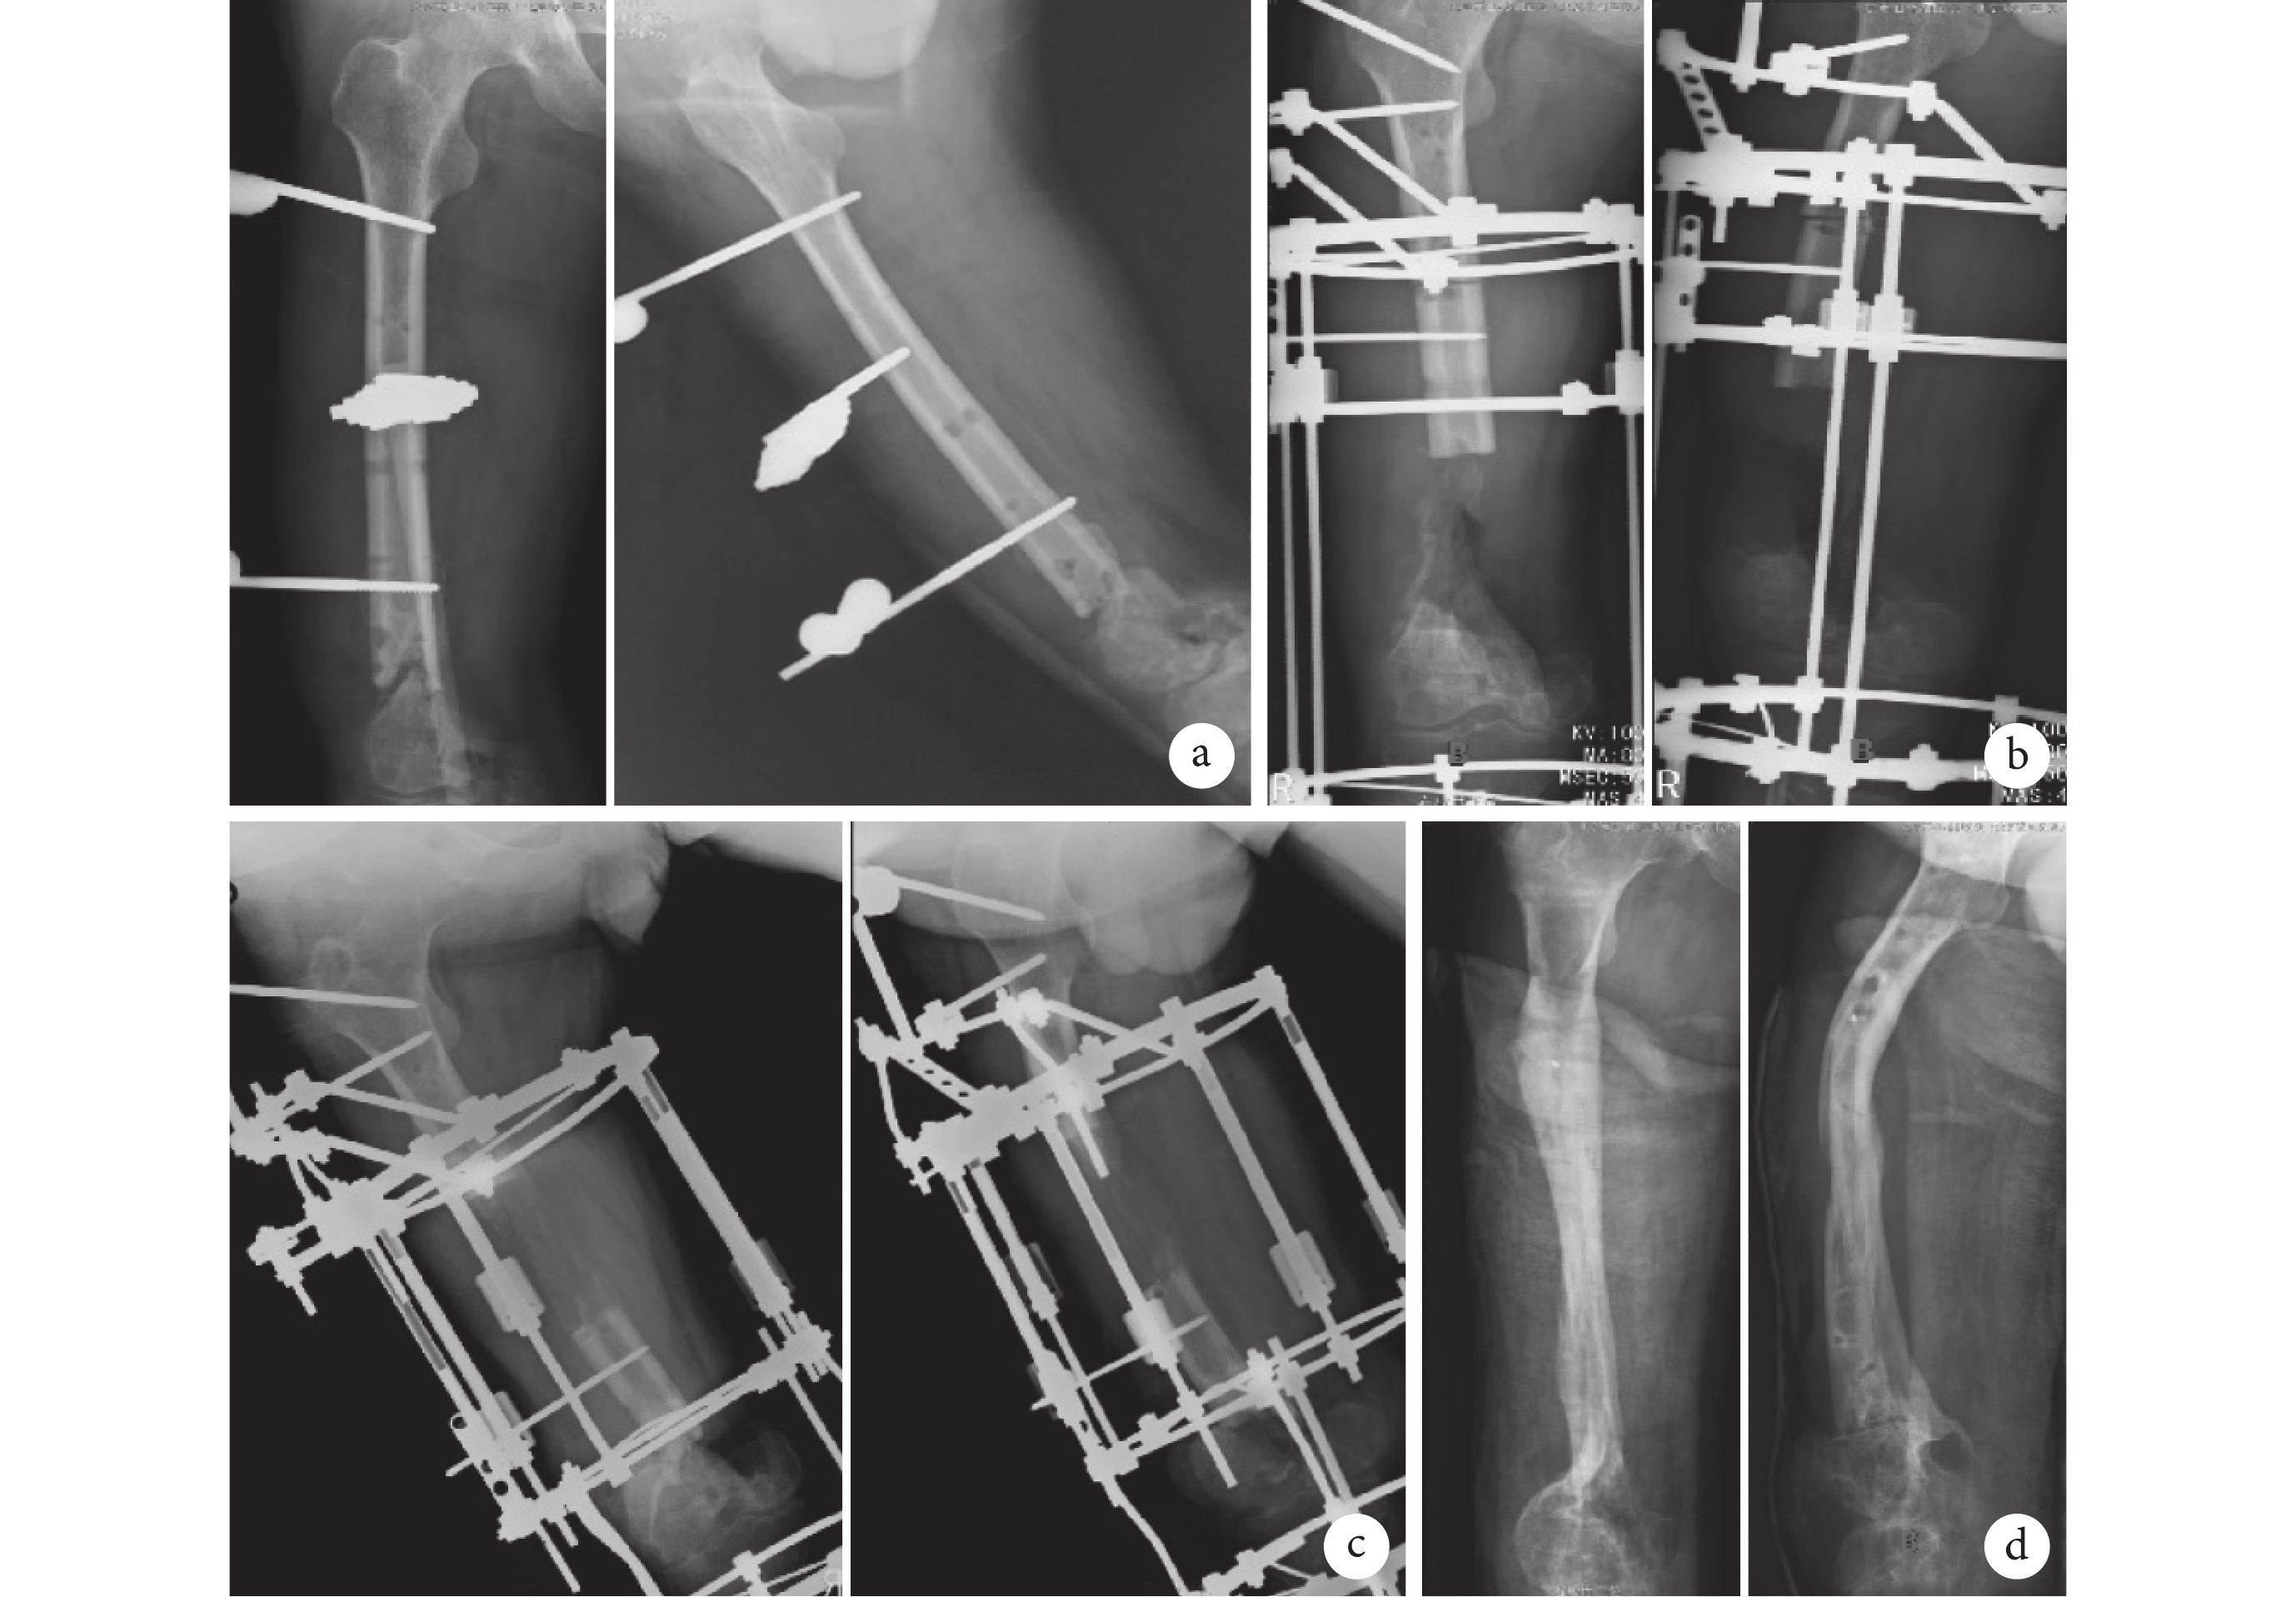

例 1 患者,女,61 歲。右股骨骨折后骨不連 9 年,既往經歷清創術、植骨術、更換鋼板、更換髓內釘、更換外固定器、再次更換鋼板等 9 次手術。骨不連位于股骨中上段。一期手術實施內固定物取出、骨不連端清理,術中骨缺損長度 2.3 cm,給予 Ilizarov 環形外固定器骨折端加壓固定手術。術后 7 d 以 0.25 mm/周速度緩慢加壓,術后 9 個月簡化外固定裝置。術后 11 個月骨不連達臨床愈合,拆除外固定。治療期間針道感染通過局部換藥控制,未更換固定針。術后 32 個月隨訪,患肢負重功能良好,按 Paley 等[6]的骨不連評價標準評價為優。術后患側肢體較健側短縮 2.4 cm。見圖 1。

圖1

典型病例 1

a. 術前 X 線片示右股骨中上段骨折,骨不連端硬化萎縮;b. 安裝 Ilizarov 環形外固定器后即刻 X 線片;c. 術后 9 個月更換組合式外固定,X 線片示骨折端愈合良好;d. 術后 11 個月拆除外固定器,X 線片示骨折端臨床愈合

Figure1. Typical case 1a. Preoperative X-ray films showed upper segment fracture of the right femural shaft with sclerosing and atrophy at nonunion site; b. Immediate X-ray films after installation of Ilizarov external fixator; c. At 9 months after operation, the Ilizarov fixator was replaced to hybrid external fixator and the X-ray films showed that the fracture healed; d. At 11 months after operation, the external fixator was removed and the X-ray films showed that the fracture clinical healed